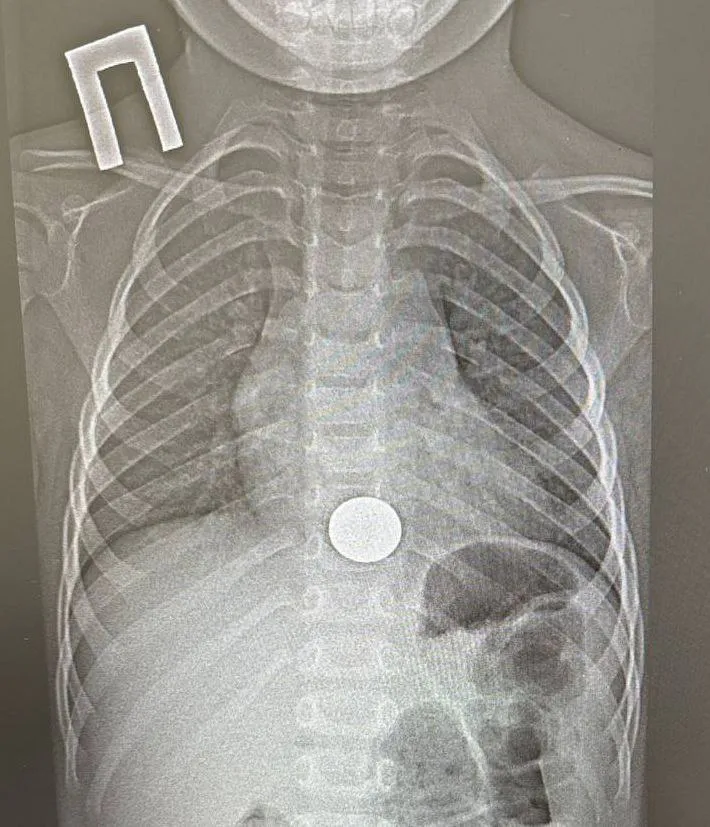

Инцидент произошёл 15 декабря. Малыш взял монету у старшего брата, случайно проглотил её и сразу рассказал об этом родителям. Мать незамедлительно доставила ребёнка в больницу. Рентген подтвердил: инородное тело застряло в пищеводе.

Операцию провёл детский хирург, врач‑эндоскопист Игорь Шогоров — он удалил монету эндоскопическим методом. Манипуляция заняла всего минуту. После наблюдения в хирургическом отделении уже на следующий день мальчика выписали домой в удовлетворительном состоянии.